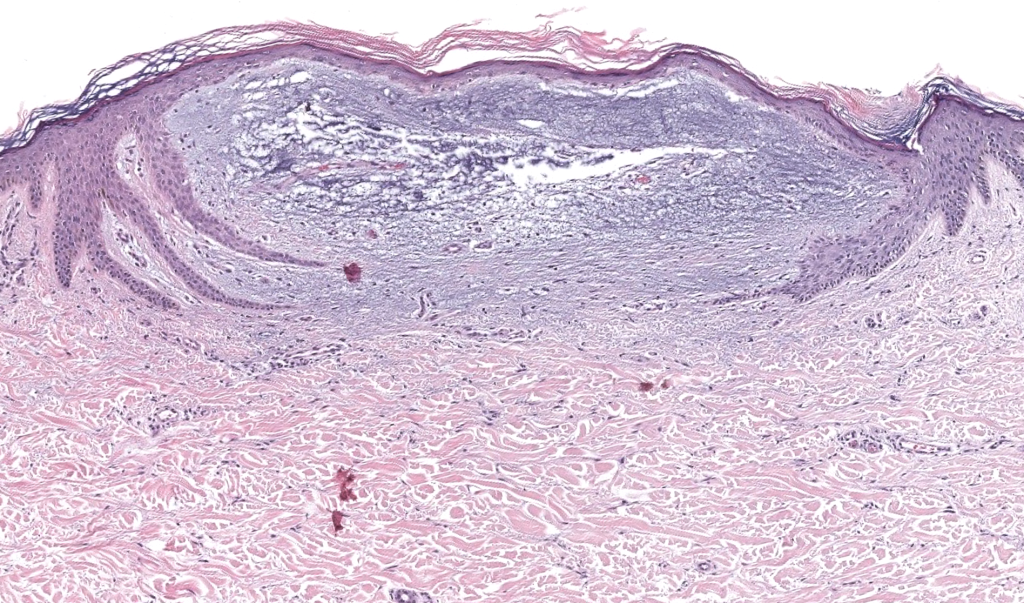

Biopsia adecuada: punch profundo/escisional; pedir Alcian blue pH 2.5, hierro coloidal y hialuronidasa(confirmar hialuronato).